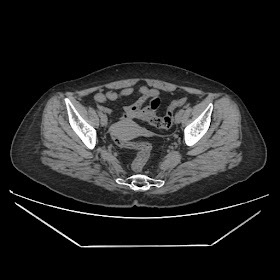

A CT abdomen revealed a left adrenal cortical tumor.

Her abdominal X-ray also reveals a right renal stone although she never complained of renal colic.

Clinician advised against surgery because she was not in pain. Her TSH is normal. A CT abdomen revealed a left adrenal cortical tumor. Diagnosis of pri. aldosteronism was made. Patient is hypertensive since 1995 since her second childbirth. Now BP is normal with medication. She is nondiabetic. Pt. advised to report her Ca2+ and K+ lvl. monthly. Pt. acq. the habit of eating paan (beetle leaf) from her mother in 2011 when she came to stay with her. Used to eat 3-4 paans a day. Stopped in 2013 after Dr. advised against it.

PATIENT'S HISTORY: The patient is a 60-year-old housewife. In 2013, she had an episode of probable stroke followed by nausea, vomiting, diarrhea, weakness, fatigue with loss of appetite, and insomnia. Her legs felt numb. She lost sensation around neck. Had to be admitted to a nursing home. Diagnosis of hypocalcemia and hypokalemia was made. Got discharged after 5 days when k+ and Ca2+ lvl. returned to normal via i.v infusion. For 2 yrs she was fine. In 2015, due to diarrhea and fatigue she got admitted to a Nursing home and stayed there for 7 days. Ca2+ and K+ lvl. was falling, so restored via i.v infusion. This time hypernatremia was also detected. Discharged after her conditions improved. But 2 days later, again due to severe diarrhea had to be admitted to a Nursing home for 19 days. During her stay USG of abdomen, colposcopy and chest X-ray was done. USG detected a large renal calculus measuring 22mm in rt. kidney. Sx was recommended. Pt went to Bhopal for a second opinion.